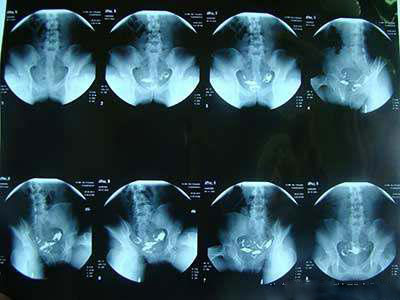

输卵管造影是提供宫颈管、官腔大小、形状和子宫轮廓情况,可明确输卵管是否通畅,并在程度上反映输卵管的形态和功能,广泛用于妇科临床,一直被认为是输卵管功能检测的首选方法。

它的优点是简便、迅速、诊断较明确,可提供输卵管内部结构信息,判断输卵管是否通畅,明确输卵管阻塞部位,较为直观的显示输卵管的柔顺度以及子宫内膜的某些病变,具有潜在的治疗作用。